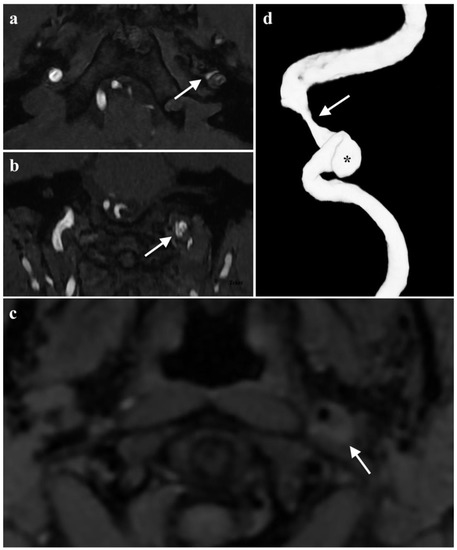

Acute Tongue Swelling as a Still Unexpected Manifestation of Internal Carotid Artery Dissection: A Case Report

The diagnosis of internal carotid artery dissection (ICAD) at the stage of local signs is essential in the prevention of the life-treating cerebral complication; however, making this diagnosis has significant difficulties. We present the case of a 36-year-old female with left ICAD with [...] Read more.

The diagnosis of internal carotid artery dissection (ICAD) at the stage of local signs is essential in the prevention of the life-treating cerebral complication; however, making this diagnosis has significant difficulties. We present the case of a 36-year-old female with left ICAD with asymmetric left-sided tongue swelling as an unusual and still unexpected symptom. The patient’s complaints at admission were left-sided numbness of the tongue and swallowing difficulties but its movements were intact. Despite the provided treatment for suspected angioedema, no improvement was noted. Additional examination revealed left-sided tongue weakness, ipsilateral soft palate palsy, paralysis and reduced tension of the left vocal fold, and left-sided Horner’s syndrome. Another suspected diagnosis was a dysfunction of the IX, X, and XII cranial nerves. A head MRI revealed an intramural hematoma of the left internal carotid artery. The radiologists suggested ICAD. The angio-MRI of the head arteries confirmed this diagnosis. The patient received dual antiplatelet therapy. The neuro-logopaedic therapy was also implemented. Currently, the patient’s symptoms are gradually improving with significantly better results on follow-up neuroimaging. Among the possible local symptoms of ICAD, proper attention should be paid to asymmetric swelling of the tongue as an atypical manifestation of damage to the hypoglossal nerve. Full article

Show Figures

Figure 1